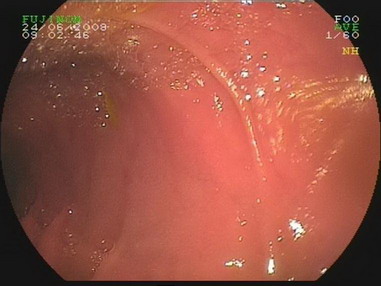

2009.6.24胃镜:

慢性浅表性胃炎,十二指肠淤滞症原因待查,肠系膜上动脉压迫综合症?(胃内可见胆汁样物反流,十二指肠球扩张,降部明显扩张,水平部远端似可见狭窄,持续充气肠腔不能打开。)